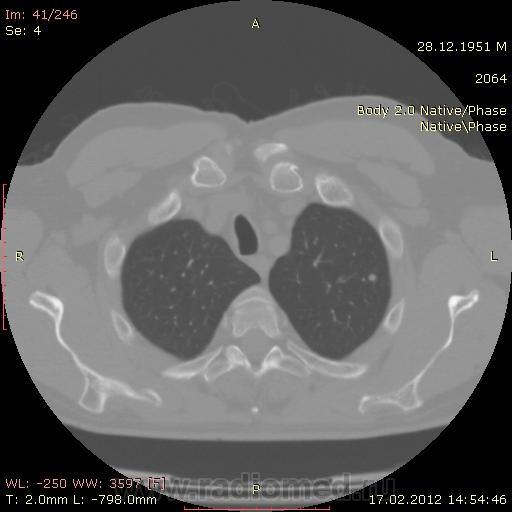

КТ.

В феврале 2012 года при очередном флюрографическом обследовании были обнаружены изменения в лёгких. По собственной инициативе было сделано КТ лёгких.